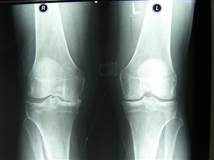

263.Науқас 45 жаста тізе буынындағы ауырсынуға шағымдануына байланысты рентгенография жасалынған. Диагноз:

*+ Деформирлеуші остеоартроз